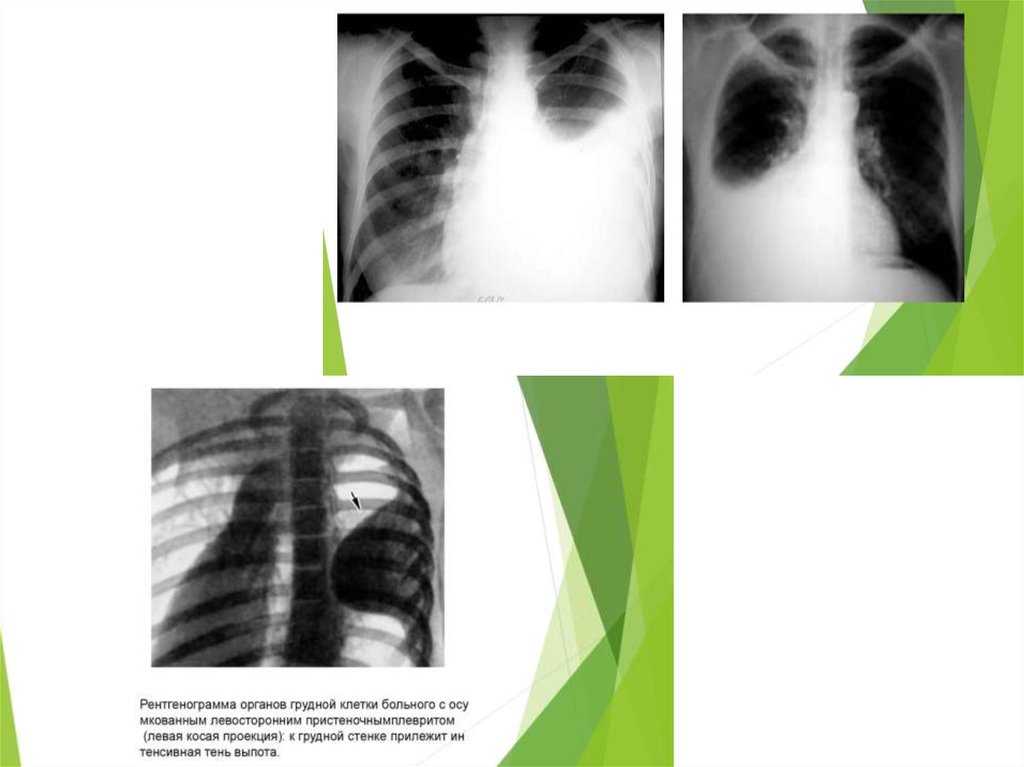

Плеврит

25. Туеркулезді плеврит